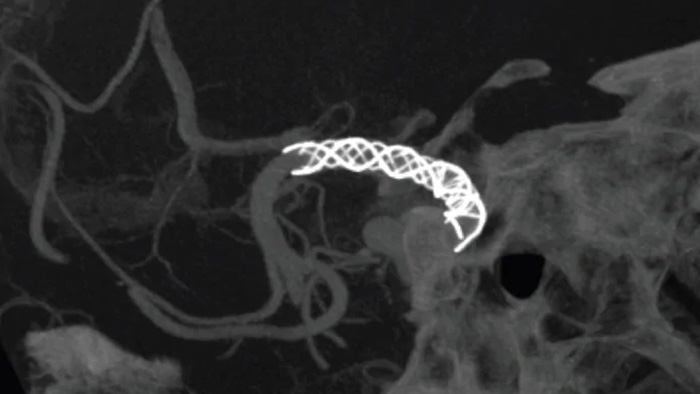

SmartCT Angio is an X-ray acquisition technique that generates a complete high-resolution 3D visualization of cerebral vasculature from a single rotational angiography run – all controlled via the touch screen at the table. This can improve visibility of tortuous or complex anatomy.

SmartCT Angio provides a volumetric view in a few seconds1 to assist assessment of location, size, neck, and severity of aneurysm for treatment planning. 3D volumes are visualized with high spatial resolution and automatic patient movement compensation.